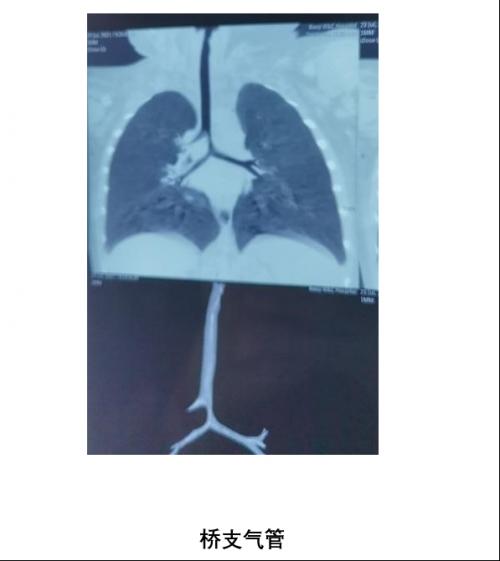

7月26日晨,气管镜中心早早做好了术前准备,内镜医师团队商讨了探查方案,对患儿实施了局麻下电子支气管镜下探查术,镜下的影像别有洞天:孩子的气管隆突位置异常,主气道软化,通过狭窄的移行段发现了隐藏在左主支气管下的真性隆突。此刻终于找到了真凶,这是一例罕见的先天性气道分支发育异常——桥支气管。是引起患儿反复呼吸道感染、咳喘、呼吸困难、喉鸣的原因之一。在与家长沟通病情后,建议进一步去上级医院做气道成形术。